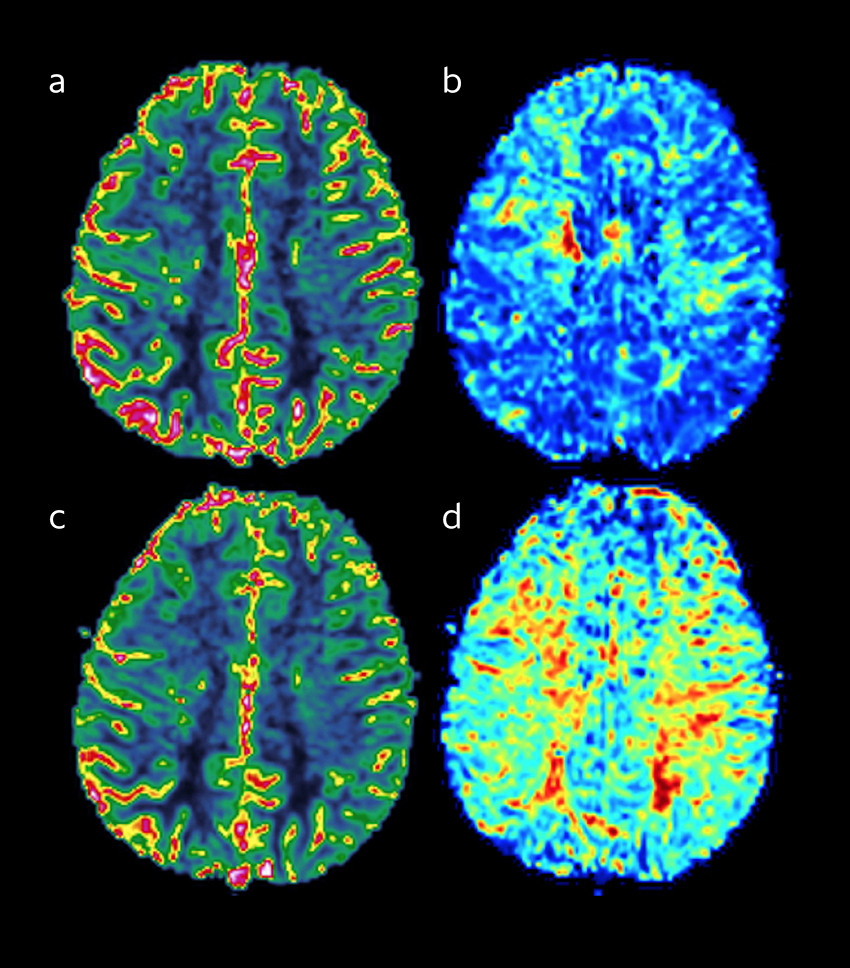

Ved hypoperfusjon vil cerebrale arterioler dilatere for å opprettholde et adekvat regionalt blodomløp. Ved kronisk hypoperfusjon vil arteriolene være predilaterte, slik at deres evne til å respondere ytterligere på en dilaterende stimulus kan være redusert. Denne evnen kalles for cerebrovaskulær reservekapasitet og kan undersøkes ved hjelp av forskjellige metoder. En dilaterende stimulus kan introduseres ved hyperkapni enten ved inhalasjon av 5 % CO2 i romluft eller intravenøs administrasjon av karboanhydrasehemmeren acetazolamid (Diamox), for dernest å dokumentere økningen av blodomløpet med transkranial dopplerultrasonografi eller MR av hodet med perfusjonsopptak (figur 2). Alternativt kan man bruke xenonforsterket CT, enfotonstomografi (SPECT) eller positronemisjonstomografi (PET).

Betydelig redusert cerebrovaskulær reservekapasitet og især invers cerebrovaskulær reservekapasitet (redusert blodomløp ved dilatativ stimulus) styrker indikasjon for kirurgisk behandling, mens normal cerebrovaskulær reservekapasitet indikerer spontant velkompensert sykdom. Transkranial dopplerultrasonografi kan også være nyttig for å følge intracerebral hemodynamikk over tid, da dette er en lett tilgjengelig og ikke-invasiv undersøkelse.